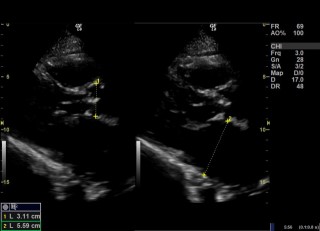

Ecocardiograma

O ecocardiograma é um exame médico não invasivo que utiliza ultrassom para criar imagens detalhadas do coração. Ele fornece informações sobre a estrutura, função e fluxo sanguíneo do coração, sendo essencial no diagnóstico e monitoramento de diversas condições cardíacas, como doenças das válvulas, insuficiência cardíaca e anomalias congênitas.

Durante um ecocardiograma, o paciente geralmente deita-se em uma mesa enquanto um técnico ou médico aplica um gel condutor na pele do peito. Em seguida, um transdutor de ultrassom é movido suavemente sobre a região do coração, emitindo ondas sonoras que são refletidas pelos tecidos do coração. Um computador converte essas ondas sonoras em imagens em tempo real, que mostram as câmaras, válvulas e estruturas do coração em detalhes.